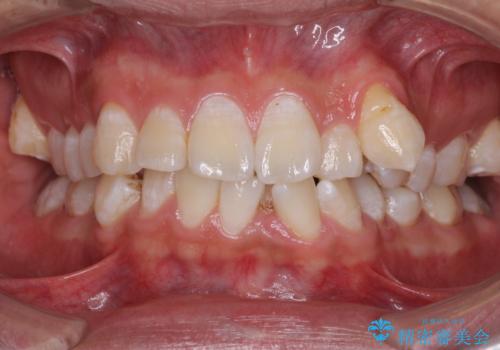

- 前歯の叢生と八重歯を気にして来院された患者様です。

叢生が強く、奥歯の咬合も左右差が大きかったため、上下左右4本を抜歯して、ワイヤー矯正を行うこととしました。